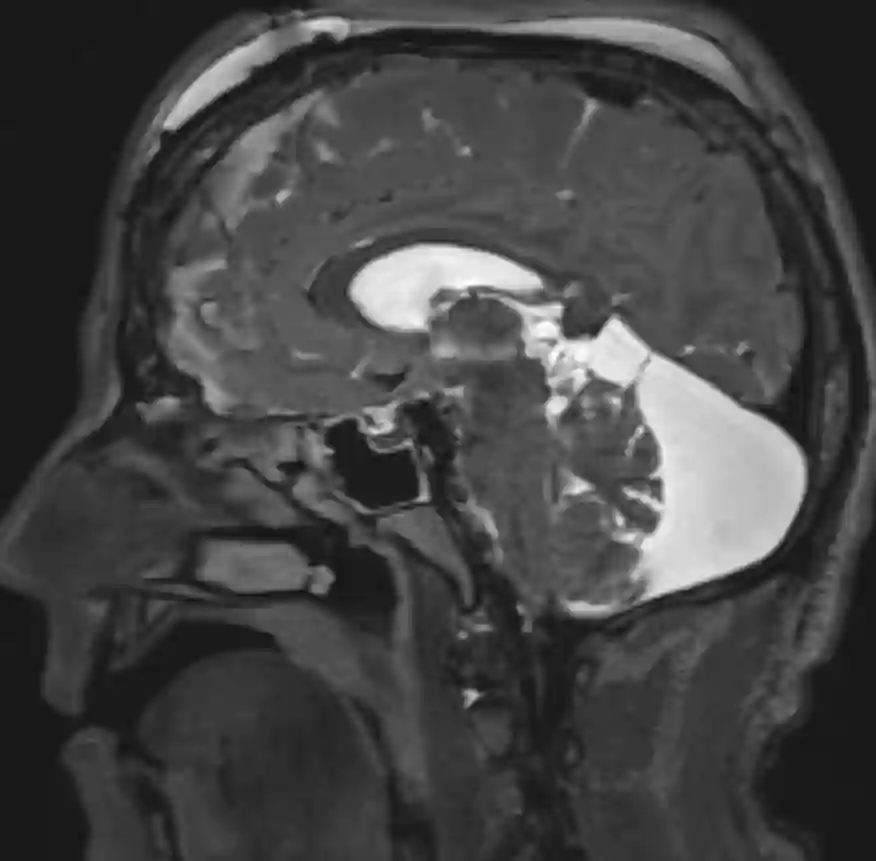

Megacisterna magna im MRI

Darstellung eines sagittalen MRI eines Patienten mit einer Megacisterna magna.